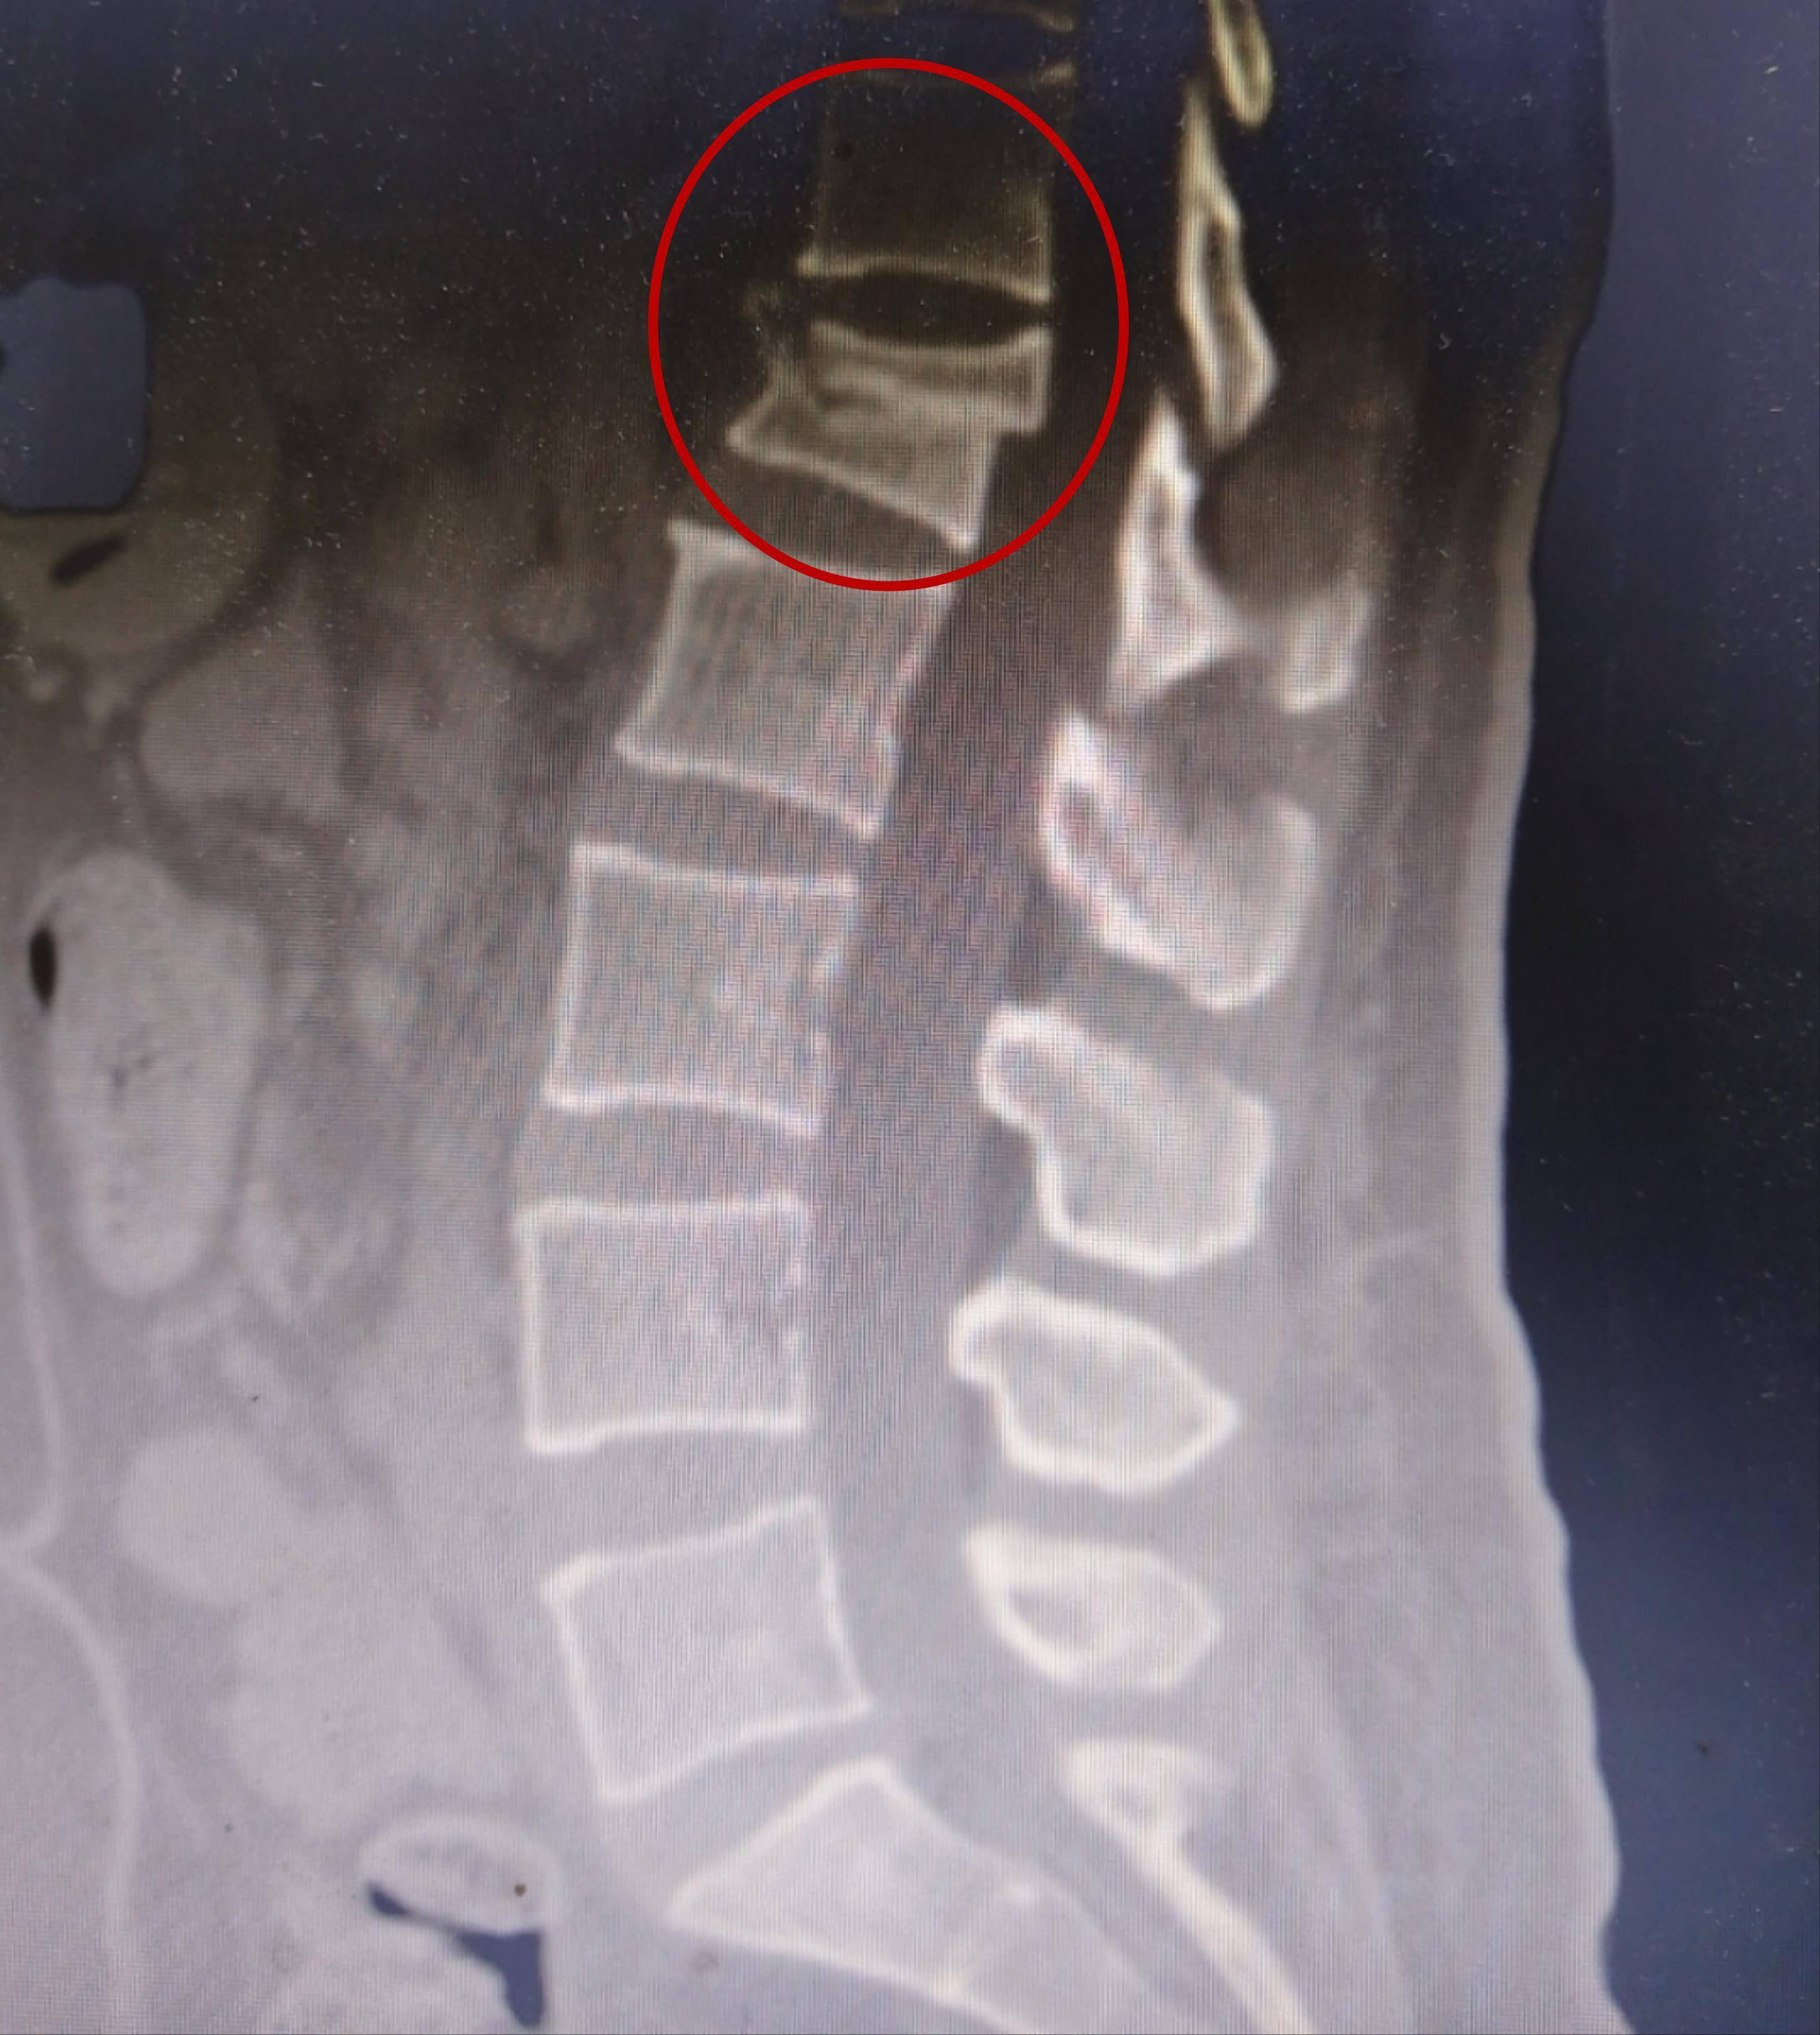

3、对于2,3,4节腰椎压缩性骨折的情况,医生通常建议至少卧床休息六个月左右这段时间内,身体需要充分恢复,以避免进一步损伤在休养期结束后,可以逐步开始进行康复训练初期阶段,建议佩戴保护支具,如夹壳背架,以提供额外支持和保护通过渐进式的训练,可以逐渐减少对支具的依赖,直至完全恢复康复训练。

5、卧床时间腰椎骨折后,患者通常需要严格卧床休息,以确保骨折部位的稳定和愈合这一卧床时间一般为23个月复查与支具使用在骨折后的12个月时,患者可以复查X线,以评估骨折的愈合情况若骨折达到一定愈合程度,患者可在医生的指导下佩戴腰部支具下床活动支具应选取有钢板固定对脊柱保护性较好的类型。

6、腰椎压缩性骨折保守治疗多久能下床,主要取决于患者骨折愈合时间及症状骨折类型较简单损伤节段较少患者又较年轻,一般一个半月可在戴护腰的情况下下床腰椎压缩性骨折的保守治疗主要采取平卧方法,轻症的年轻患者要在二周四周或一个半月复查片子,观察骨折有无进一步进展,是否出现愈合,复查后可以遵。